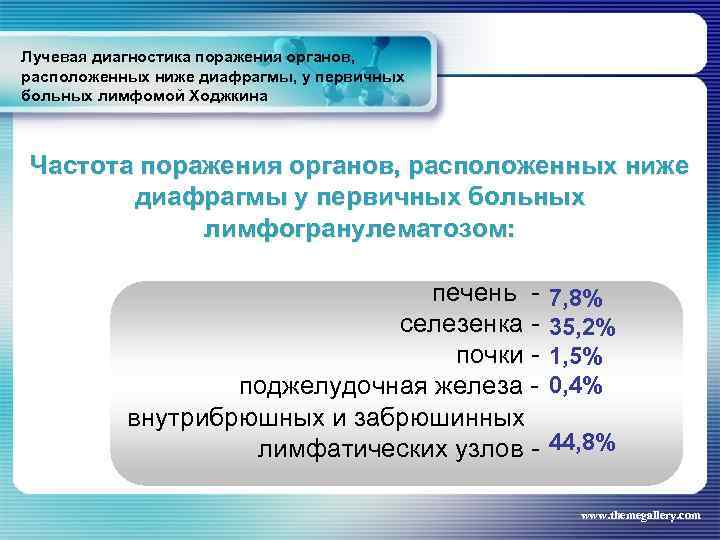

Лучевая диагностика поражения органов, расположенных ниже диафрагмы, у первичных больных лимфомой Ходжкина Частота поражения органов, расположенных ниже диафрагмы у первичных больных лимфогранулематозом: печень селезенка почки поджелудочная железа внутрибрюшных и забрюшинных лимфатических узлов - 7, 8% 35, 2% 1, 5% 0, 4% 44, 8% www. themegallery. com

Лучевая диагностика поражения органов, расположенных ниже диафрагмы, у первичных больных лимфомой Ходжкина Частота поражения органов, расположенных ниже диафрагмы у первичных больных лимфогранулематозом: печень селезенка почки поджелудочная железа внутрибрюшных и забрюшинных лимфатических узлов - 7, 8% 35, 2% 1, 5% 0, 4% 44, 8% www. themegallery. com